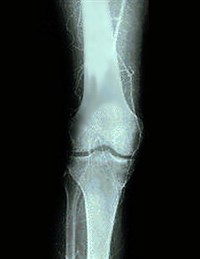

Ангиография — рентгенологическое исследование кровеносных сосудов. Осуществляется с помощью специальных рентгеноконтрастных препаратов, которые вводятся в кровеносное русло. Ангиография производится для выявления заболеваний самих сосудов (атеросклероза, эндартериита, флеботромбоза, недостаточности клапанного аппарата вен), а также при диагностике ряда доброкачественных и злокачественных заболеваний внутренних органов.

При исследовании артерий конечностей рентгеноконтрастный препарат вводится в магистральный артериальный сосуд выше места предполагаемого поражения, после чего на мониторе прослеживают продвижения контраста по артерии, делается серия рентгеновских снимков. При наличии патологии артерии (чаще всего это проявляется сужением ее просвета), выявляется уровень поражения, наличие коллатералей (окольного перетока крови). Для исследования артериального русла внутренних органов — сердца, почек, печени, кишечника — контрастное вещество вводится с помощью специального катетера непосредственно в артерии исследуемого органа. С помощью ангиографии могут выявляться заболевания внутренних органов, за счет изменения «сосудистого рисунка» — появления дополнительных сосудов или, наоборот, исчезновения ряда сосудов. Рентгенологическое исследование вен называется флебографией и чаще всего производится для выявления заболеваний вен нижних конечностей.